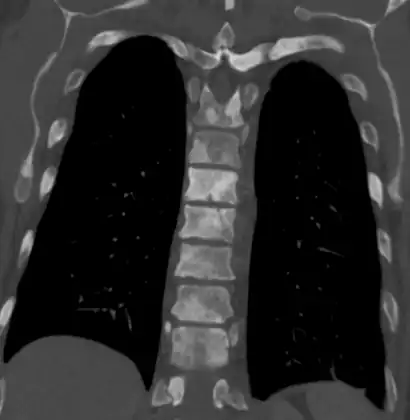

-

Sclerosis of the bones of the thoracic spine due to prostate cancer metastases (CT image) -

The most important distinction made by any staging system is whether the cancer is confined to the prostate. In the TNM system, clinical T1 and T2 cancers are found only in the prostate, while T3 and T4 cancers have metastasized. Several tests can be used to look for evidence of spread. Medical specialty professional organizations recommend against the use of PET scans, CT scans, or bone scans when a physician stages early prostate cancer with low risk for metastasis.[95] Those tests would be appropriate in cases such as when a CT scan evaluates spread within the pelvis, a bone scan looks for spread to the bones, and endorectal coil magnetic resonance imaging evaluates the prostatic capsule and the seminal vesicles. Bone scans should reveal osteoblastic appearance due to increased bone density in the areas of bone metastasis—the reverse of what is found in many other metastatic cancers.